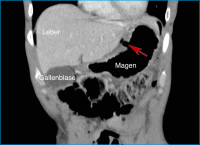

Abbildung 2: Die 3D-Rekonstruktion des CT in parakoronaler Schnittführung zeigt die Lokalisation des Ulkus noch anschaulicher.